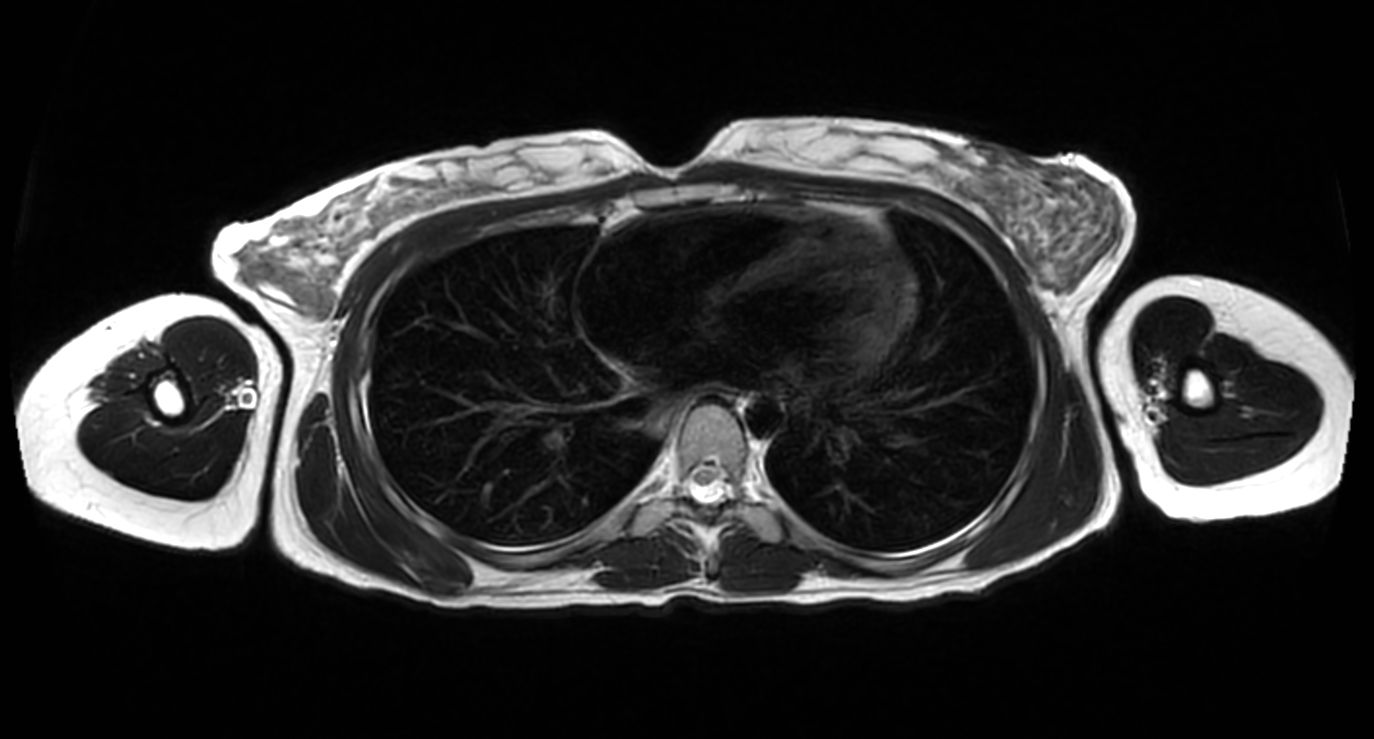

T1w mDIXON XD (In Phase)